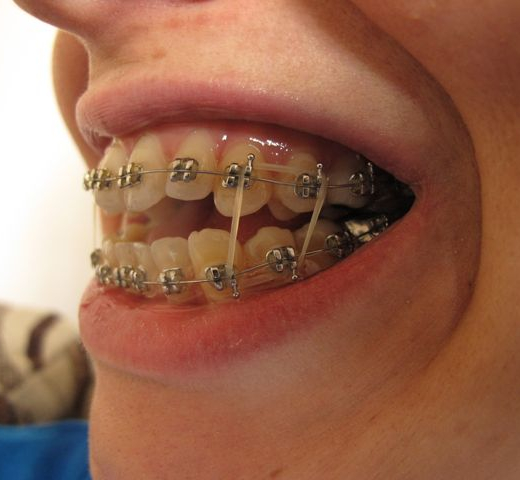

Treatment options range from non-surgical methods, like wiring the jaws shut for minor fractures, to surgical interventions using plates, screws, and wires to secure the bones for more severe fractures.